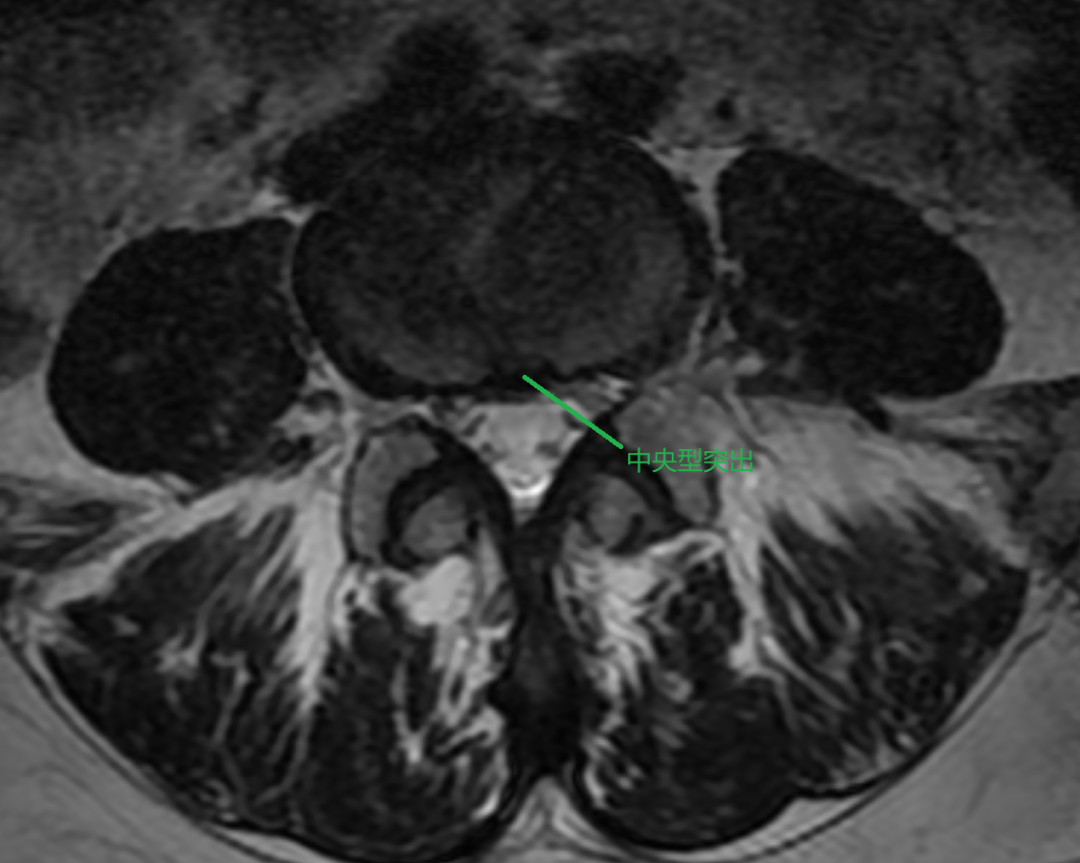

①中央型突出(少见)

女性,48 岁, L4/5 椎间盘突出,中央型